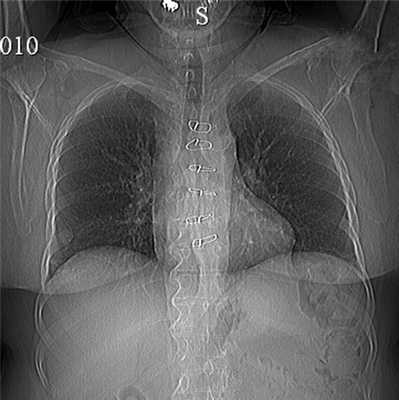

На догоспитальном этапе по месту жительства больным выполнена рентгенография грудной клетки, которая малоинформативна в диагностике остеомиелита грудины, особенно при подозрении на инородное тело, из-за наложения на рисунок тени средостения в прямой проекции, отека, инфильтрации и послеоперационных рубцовых изменений в боковой проекции (рис. 1). Рисунок 1. Рентгенограмма грудной клетки больной Г., 57 лет. Определяются витки стальной проволоки после остео синтеза, визуализировать электрод в нижней трети гру дины невозможно.

Обзорная рентгенограмма грудной клетки в двух проекциях: легочные поля изменены по типу диффузной эмфиземы, структура корней легкого без изменения. В проекции грудины определяются петли стальной проволоки после остеосинтеза, визуализировать электрод в нижней трети грудины - невозможно (см. рис. 1).